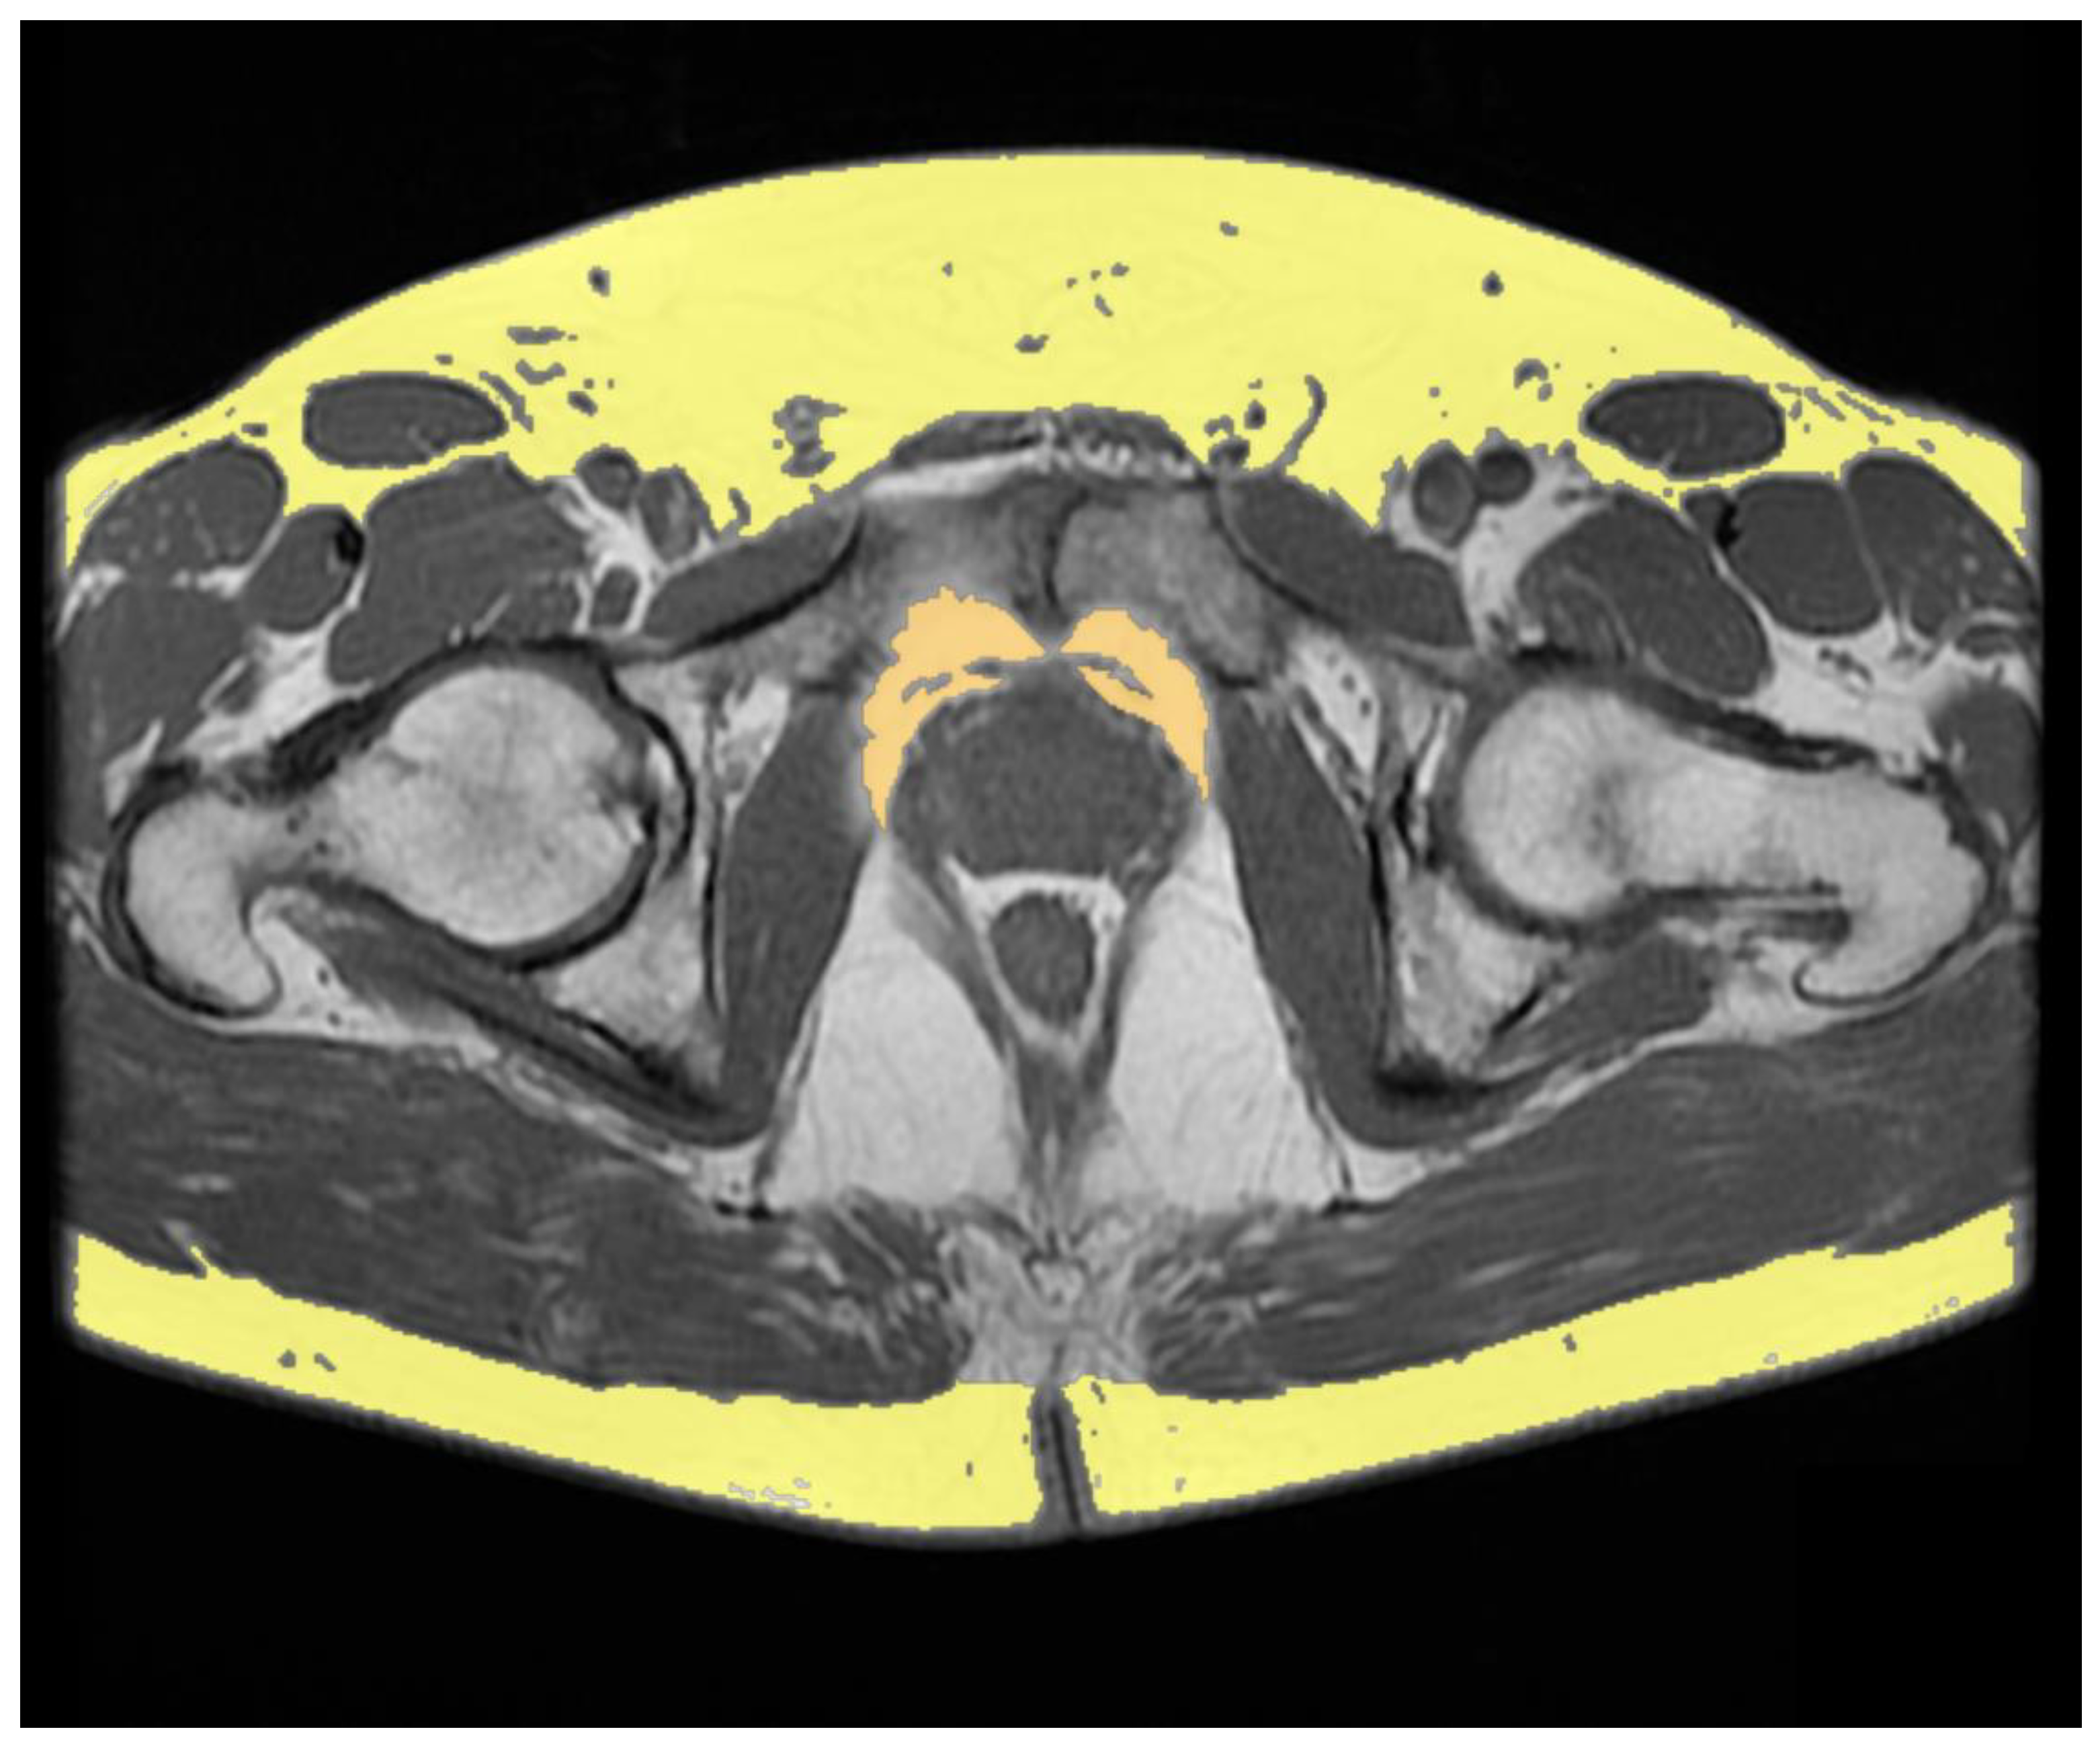

| Salji et al. (2018) [20] | Luteinizing hormone-releasing hormone analogues Androgen receptor blocker alone Estrogen patches Luteinizing hormone-releasing hormone antagonist | PPFV | Volume was calculated by consecutive areas using MRI-based approach on T2-weighted axial images | 61 | Higher PPFV in castration-resistant PCa patients compared to patients who showed a prolonged response to ADT (p < 0.0001). |

| Sasaki et al. (2020) [21] | Luteinizing hormone-releasing hormone agonist or antagonist Androgen blockade | Periprostatic adipose tissue thickness SAT thickness VAT SAT | Periprostatic fat thickness was measured on T2-weighted axial images at the femoral head and greater trochanter of the femur levels SAT thickness was measured on T2-weighted axial images at the maximum diameter of the bladder level VAT and SAT areas area were measured on axial plane using CT-based approach at the level of the umbilical position | 85 | Periprostatic adipose tissue/SAT thickness ratio ≥ 1 and overall survival Periprostatic adipose tissue/SAT thickness ratio < 1 and overall survival Univariate hazard ratio and multivariate hazard ratio showed p = 0.043 and p = 0.002, respectively VAT/SAT thickness ratio ≥ 1 and <1: no significant difference |